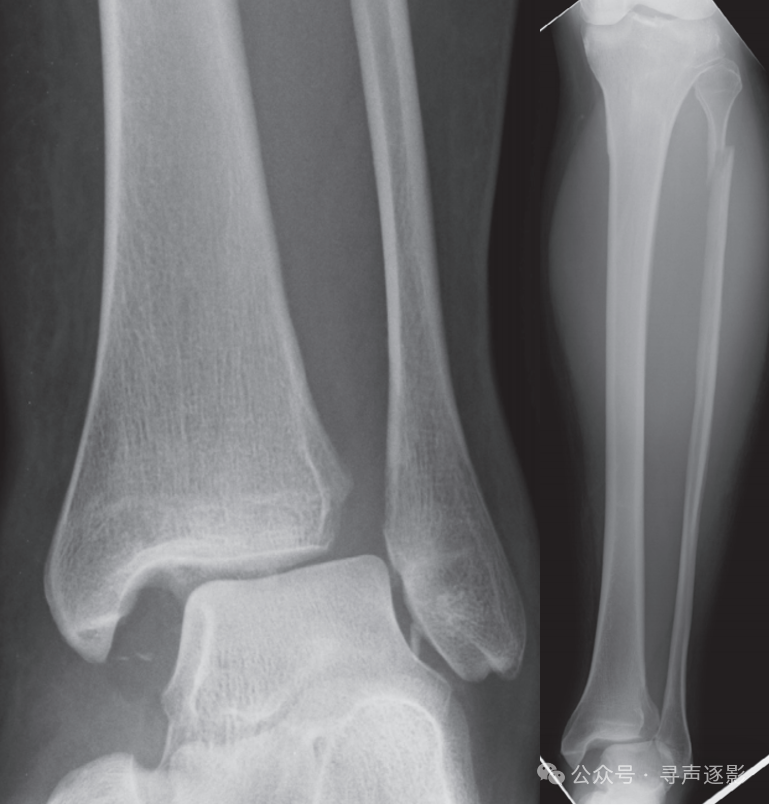

胫骨远端Salter-Harris Ⅱ型骨折。Ⅱ型骨折是所有累及骺板的骨折中最常见的一类。

左图:距骨颈骨折,移位(箭头)。右图:距骨颈骨折,无移位(箭头)。